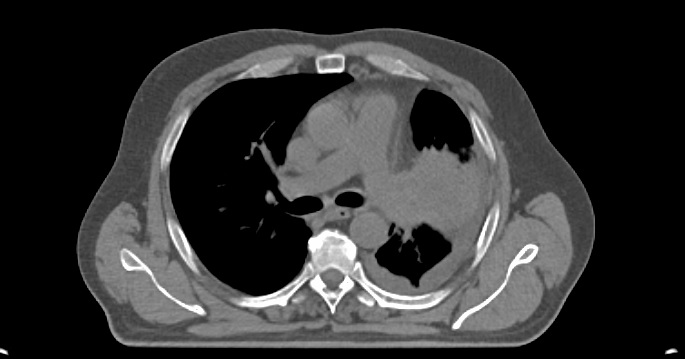

Pacientul M.L. in varsta de 56 ani, fumator de 40 ani, 20PA, s-a prezentat in clinica noastra pe data de 30.11.2022, cu diagnosticul de adenocarcinom pulmonar (neoplasm pulmonar) la nivelul lobului pulmonar superior stang, o tumora in stadiul IIIC, de dimensiuni mari T3, cu invazie ganglionara si mediastinala. Cazul a fost prezentat in Comisia Oncologica Multidisciplinara a clinicii noastre, unde s-a decis initierea tratamentului oncologic. Tumora fiind avansata loco-regional, era exclusa interventia chirurgicala in acest stadiu de boala (cancer pulmonar inoperabil).

Astfel, in perioada 5.12.2022 – 26.01.2023, pacientul a efectuat radioterapie externa cu fotoni, tehnica VMAT-CBCT, pana la doza totala DT = 66 GY/volum tinta formatiune tumorala pulmonara, un numar total de 33 fractii, concomitent cu administrarea saptamanala de polichimioterapie de radiosensibilizare, cu toleranta foarte buna.

Prezentam acest caz la scurt timp dupa finalizarea tratamentului (tratament cancer pulmonar), deoarece acesta este un caz fericit, la care s-a observat un raspuns aproape total chiar din timpul tratamentului RT, imaginile CBCT efectuate la inceputul, in timpul si la finalul tratamentului RT, pe care le atasam, aratand clar un raspuns extraordinar de bun la tratamentul efectuat.